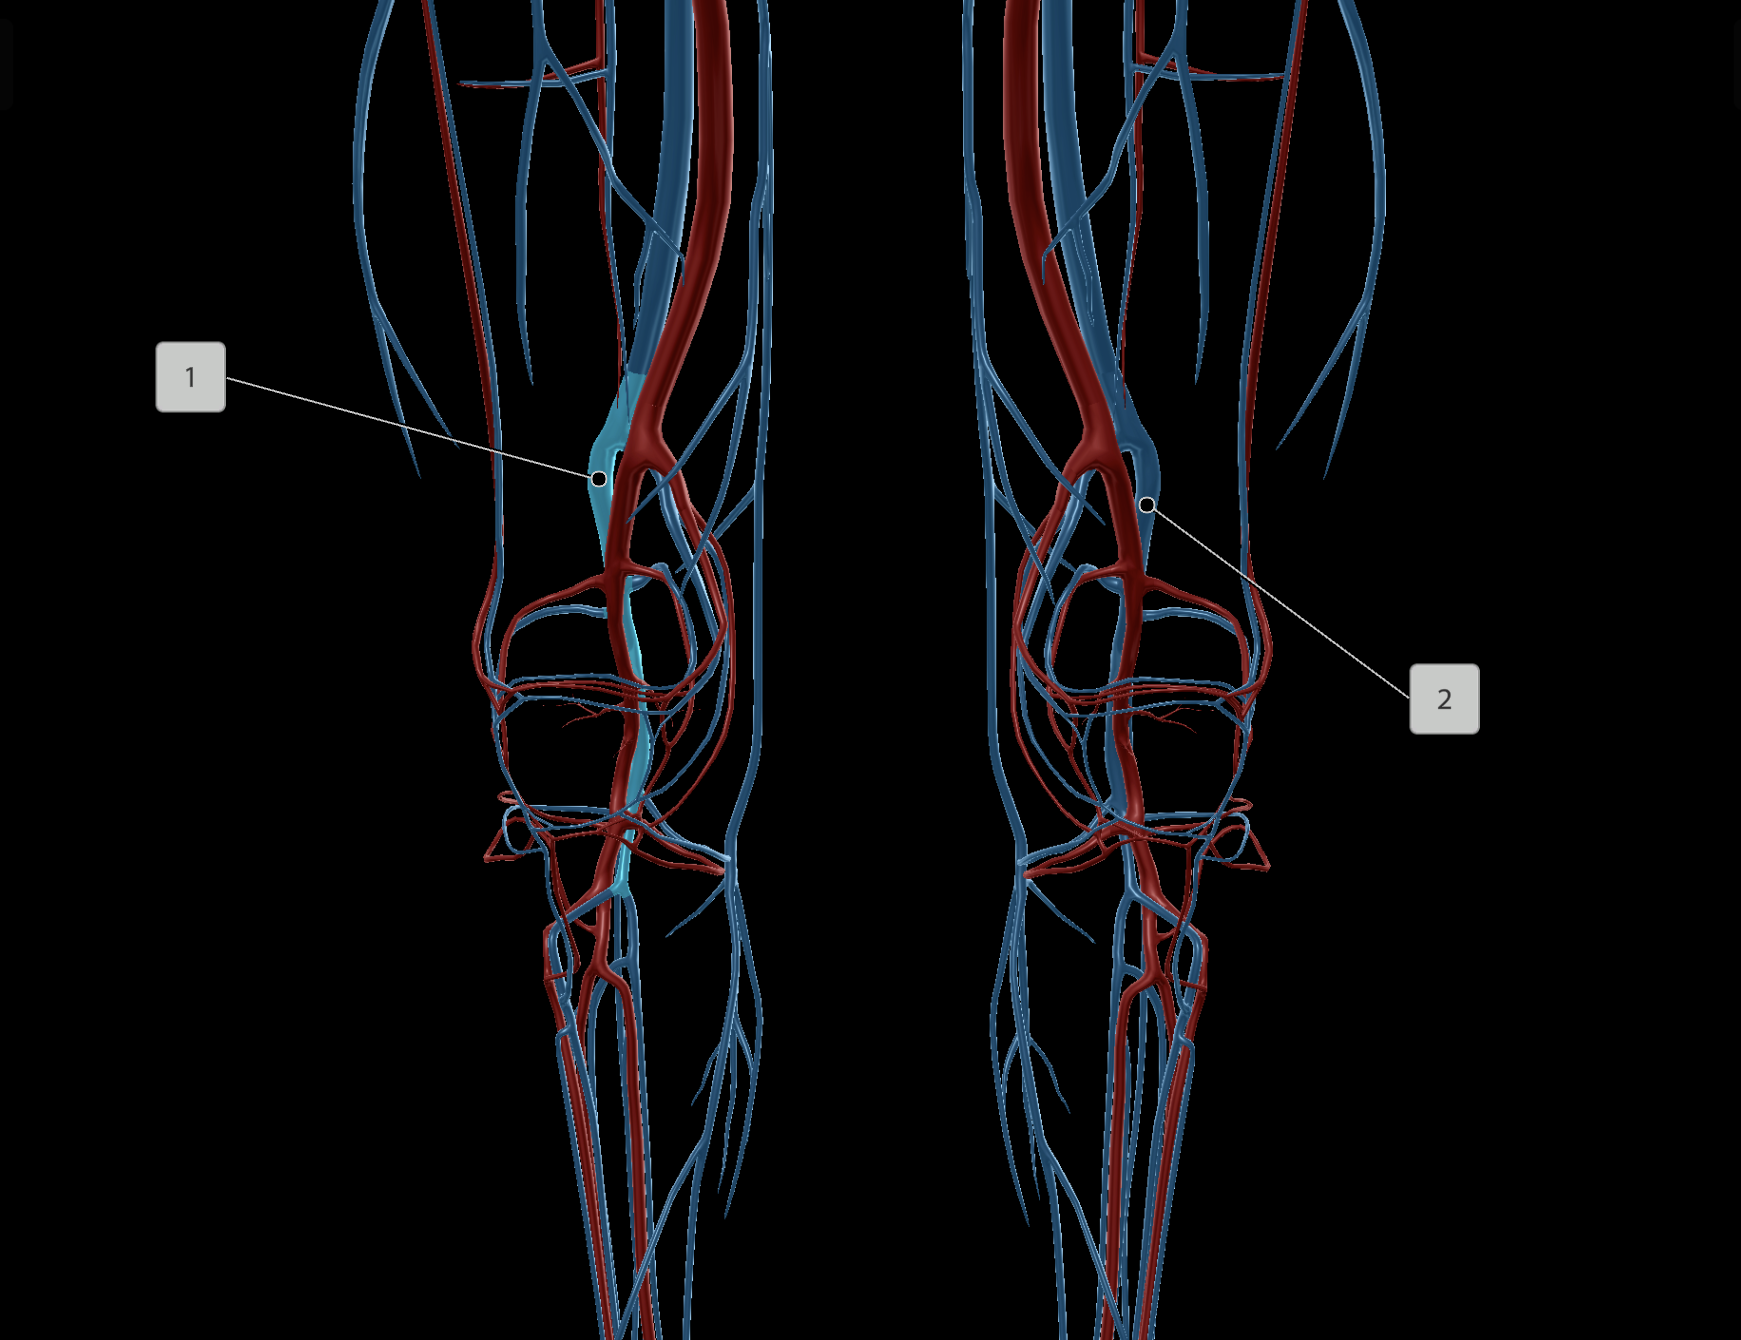

Femoral Artery

Popliteal Artery

Femoral Vein

Popliteal Vein

Deep Femoral Artery